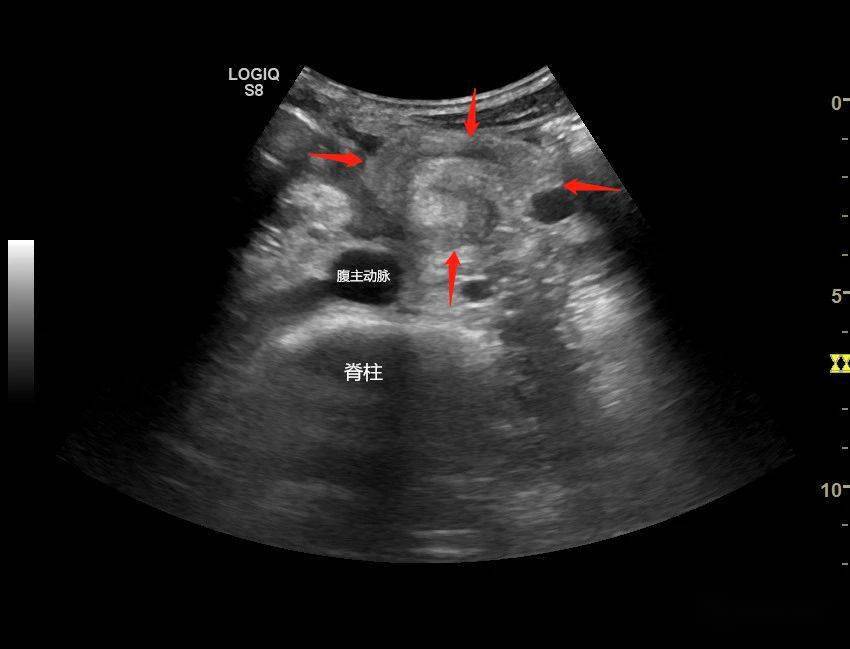

腹主动脉与肠系膜上动脉的夹角小于正常值十二指肠降部,水平部近段增

肠系膜淋巴结肿大

上图:彩超检查,可以显示肠系膜上动脉和肠系膜上静脉呈扭转状的位置